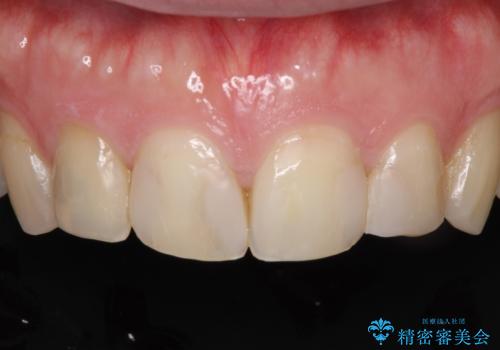

前歯の治療。再根管治療~セラミッククラウン